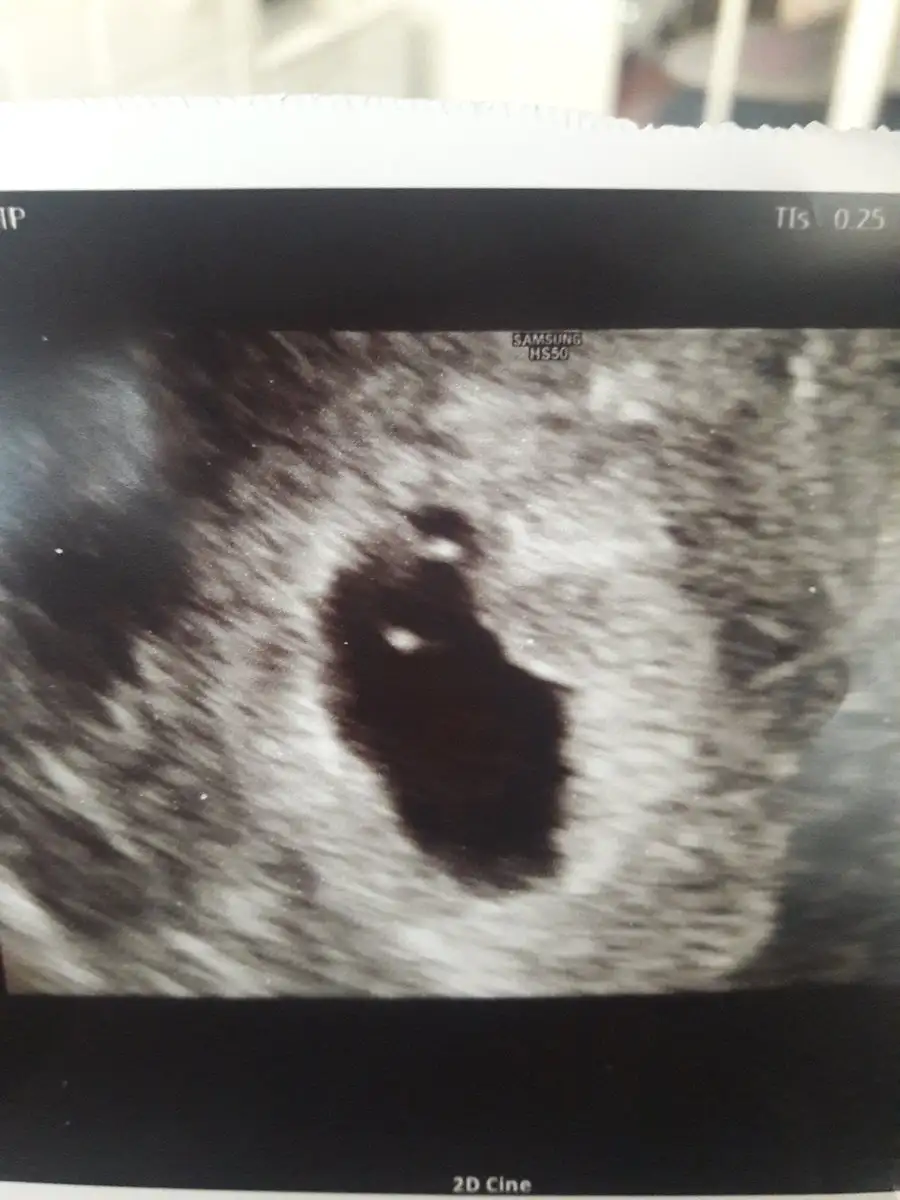

Ben de doktora gittim bugün. Daha büyük sanıyorduk sat ' a göre fakat henüz 5 hafta 4 günlükmüş. Henüz küçükmüşüz ama Yine de buyrun kesemiz, yolk sac'ımız ve hemen sağında keseye bitişik olan pek anlaşılmayan bir yapıdaki halimiz.kalp atışımızı da gördük elhamdülillah. Darısı gün bekleyenlerin başına... Eki Görüntüle 2202575